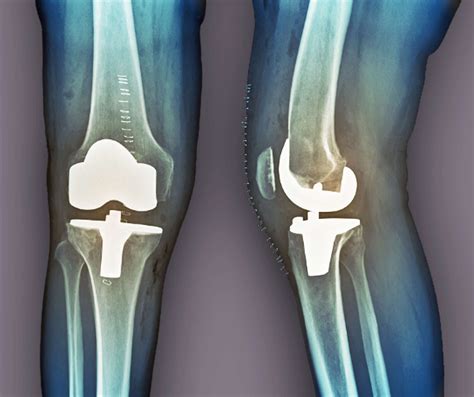

• Total Joint Replacement: This involves replacing the entire joint with an artificial implant. Common examples include total hip replacement and total knee replacement.

• Partial Joint Replacement: In this procedure, only the damaged portion of the joint is replaced. For example, a partial knee replacement may be performed if only one compartment of the knee is affected.

• Surgery: The surgical procedure involves making an incision to access the joint, removing the damaged bone and cartilage, and replacing it with an artificial implant. The type of implant used depends on the specific joint and the extent of the damage.